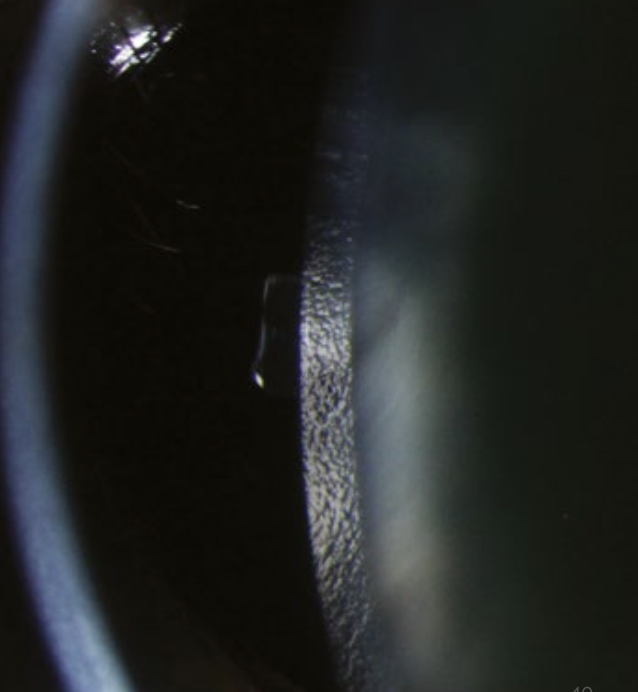

What is the “beaten metal” (peau d’orange) appearance of the lens, and when is it seen?

→ viewed with a slit-lamp using oblique illumination, the anterior capsule of the lens shows a “beaten metal” or “orange peel” (peau d’orange) appearance

occurs because the lens surface is not perfectly smooth, giving it a fine, textured reflection that resembles hammered metal